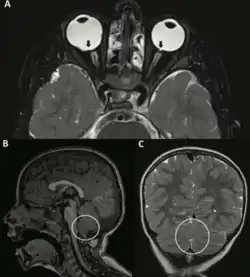

Decreased tone of muscles is most noticeable in early life, causing feeding difficulties and constipation in infants, and further impeding the development of speech and motor skills in children. Epilepsy and seizure disorders affect over one-third of individuals, while some individuals encounter motor and movement disorders. Eye involvement can lead to vision, movement and alignment issues, and ear involvement may result in hearing loss. Affected individuals may at times demonstrate benign brain malformations in neuroimaging studies.[4]